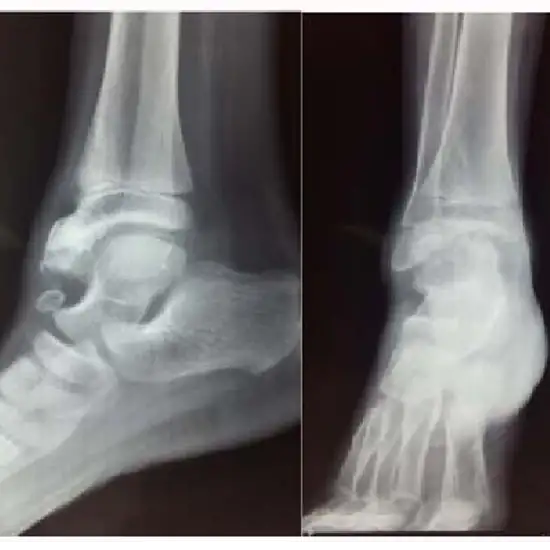

X-ray Both Ankle Lateral

X-Ray Both Ankle LAT is used to see the ankle bones and the soft tissues around them (skin and muscles).

The doctor gives this test to find out if any bones in the ankle joint are broken or fractured and check how the broken bone is healing.